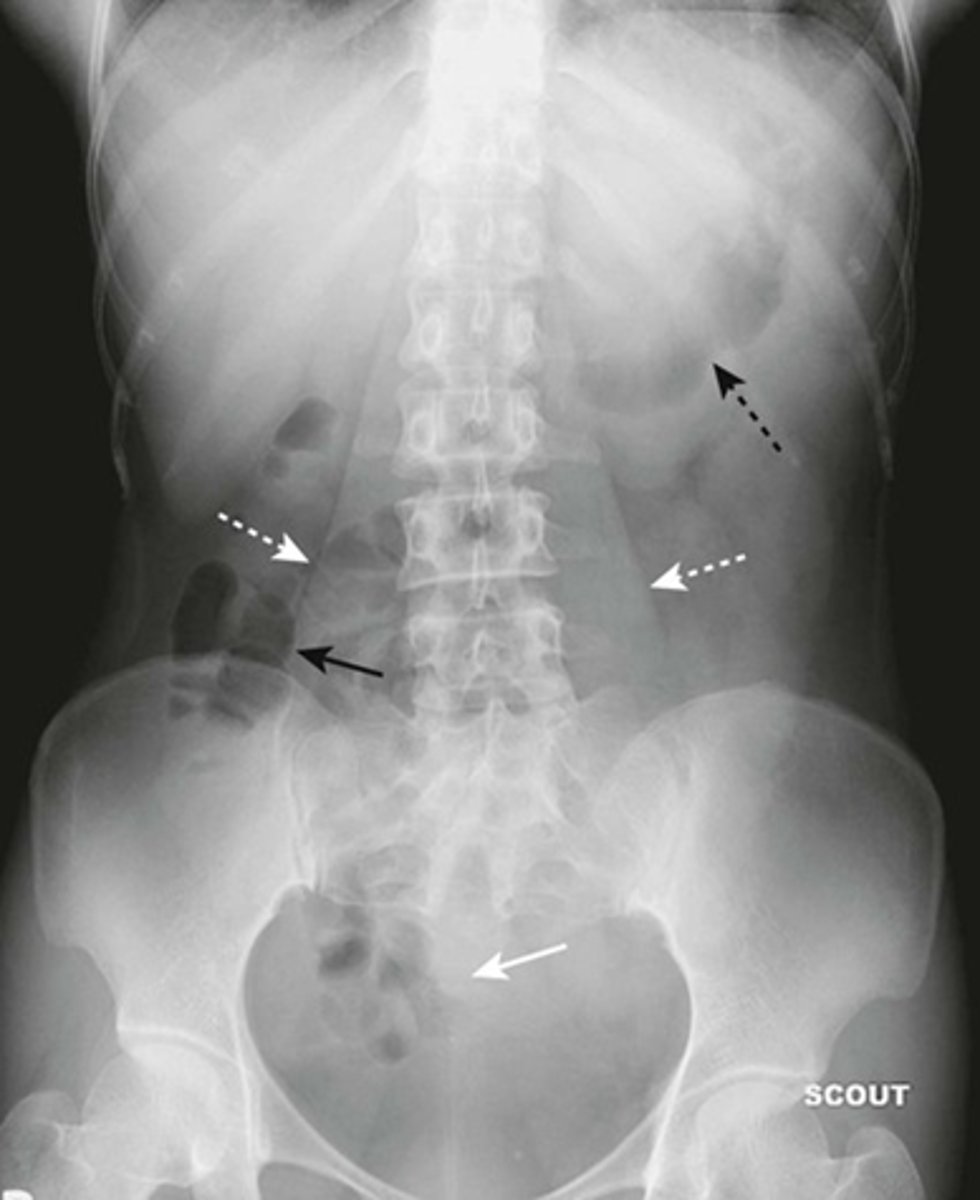

Normal supine abdomen

SOLID BLACK ARROW: small amount of air in about two or three loops of nondilated small bowel

DOTTED BLACK ARROW: air in stomach, always will have.

SOLID WHITE ARROW: air in the rectosigmoid colon.

DOTTED WHITE ARROWS: psoas muscles outlined by fat.